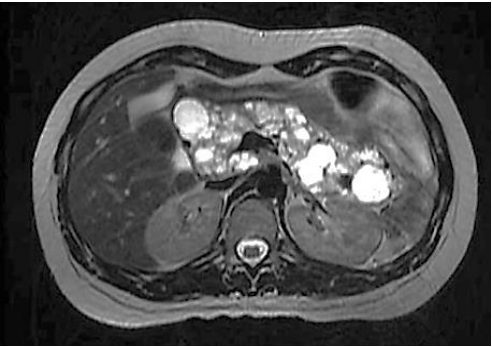

Paciente realiza ressonância magnética que individualiza múltiplas formações císticas pancreáticas, conforme a imagem a seguir:

Fonte: Arquivos Brasileiros de Endocrinologia e Metabologia, v. 43, n. 5, out. 1999.

Nesse caso, o paciente não possui maior risco de desenvolver: